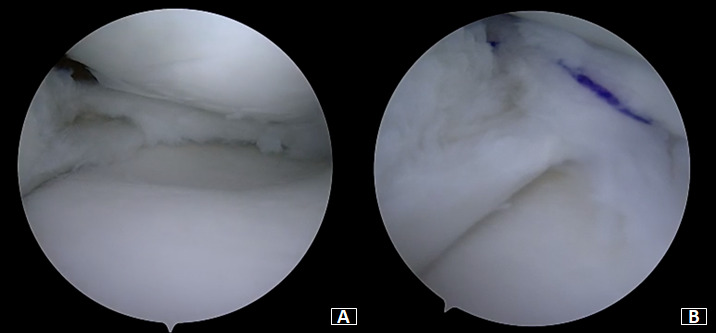

Under general anesthesia, a left knee arthroscopy using standard anterolateral and anteromedial portals. An incomplete type medial discoid meniscus with an atypical hypertrophic posterior root and an enlargement of the body and the posterior horn of the meniscus was found (Figure 3A). In addition, instability of the posterior horn, with a lack of rear tibial attachments, was observed (Figure 3B). Saucerization of the central discoid element was performed until an average meniscal width and semilunar shape was reached (Figure 4A). Two outside-in sutures with absorbable stitches were thus applied to repair the horizontal tear and stabilize the meniscus’s peripheral rim to the knee capsule (Figure 4B). A probe was used to assess the repair’s tightness and stability. Because the right knee was paucisymptomatic, no treatment was performed.

Patel et al.16 recommended preservation of the discoid meniscus in asymptomatic or minimally symptomatic patients and encouraged saucerization of a torn symptomatic discoid meniscus. Meniscectomy has been for many years the standard treatment for symptomatic discoid meniscus. However, different studies demonstrated that total meniscectomy increases the risk of osteoarthritis compared with partial meniscectomy.17,18 Nowadays, more conservative treatments are gaining support, being suture of meniscal tears and meniscal preservation even more popular. Arthroscopic saucerization and peripheral suture repair are also proposed surgical treatments for symptomatic discoid meniscus.5,8 Flouzat-Lachaniette et al.1 described four cases of discoid medial menisci treated with meniscoplasty, removing only the central part of the meniscus, and one case with associated meniscal repair demonstrating satisfactory results. Cho et al.19 reported a case of bilateral discoid medial menisci with unilateral symptoms. The patient was treated with good final results by cauterization and all-inside repair of the anterior horn tear. Similarly, in our case, we performed saucerization of the hypertrophic portions and suture of the associated lesions of the symptomatic discoid medial meniscus. Saucerization of the central discoid meniscus was performed first until a regular semilunar shape with a normal width was obtained. Unlike Cho et al.,19 which performed an all-inside repair of the anterior horn, in our patient, the repair was performed in the posterior horn, which appeared unstable and with a horizontal tear, through an outside-in technique.